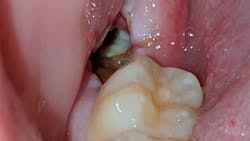

Alveolar osteitis or “dry socket” is one of the most common complications associated with extraction of teeth, especially mandibular third molars. The pathophysiology, causes, and treatment are often debated even to this day due to a complex and multifactorial etiology which is why I have cited a single comprehensive review. Birn, in a series of articles from 1963–1977, noted the pathophysiology of alveolar osteitis to be a fibrinolysis of the postextraction blood clot within the extraction socket. Dissolution and/or exfoliation of the blood clot, before the formation of sufficient granulation tissues, then exposes the remaining alveolar bone and associated nerves within the extraction site to air, debris, bacteria, and saliva which may irritate the area, producing symptoms for the patient. The result is pain, which may be localized or radiate to the ear, possible swelling of the area, and occasionally a bad odor in the mouth.

Treatment of alveolar osteitis, in my experience, consists of debriding the area with irrigation of the site and, if necessary, instrumentation of the socket to remove debris from the site. An obtundent dressing is then placed into the extraction site using Iodoform gauze or Gelfoam as a carrier. The medicament compound placed onto the carrier/dressing varies by personal preference. These compounds usually consist of an analgesic (eugenol), topical anesthetic (benzocaine), and antimicrobial (Iodoform). This dressing covers and quiets exposed nerves and physically prevents debris from entering the extraction site.